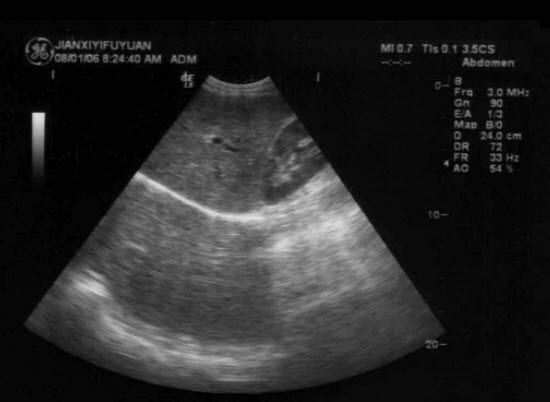

某患者脾脏声像图表现如图,诊断为()

A.正常脾脏

B.脾大

C.脾破裂

D.脾梗死

E.以上都不是